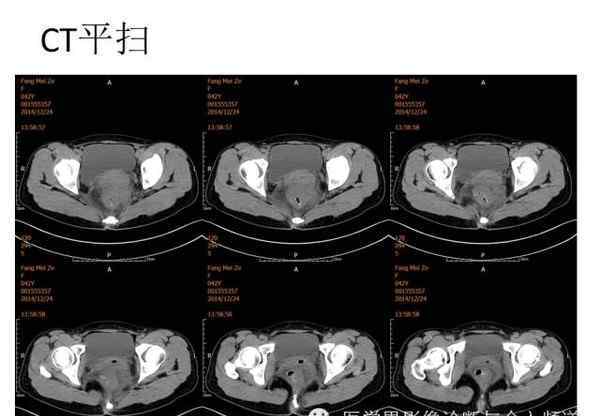

[图片图片]

[图像特征]

核磁共振平片扫描和增强扫描显示:

盆腔内可见弥漫性长T1长T2异常信号,FS-T2WI可见高信号,涉及直肠左前壁、直肠侧韧带和宫颈等。边界不清,盆腔可见条带状FS-T2WI高信号强度。注射钆喷酸葡胺后,病情明显加重。